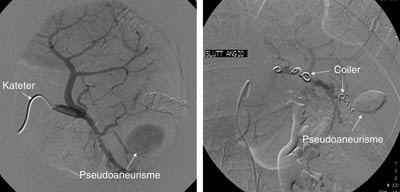

Pasient 1. En 16 år gammel gutt ble henvist til lokalsykehuset med spørsmål om miltskade. Han hadde seks dager tidligere falt under fotballtrening. Pasienten kom gående og klagde over magesmerter. CT-undersøkelse supplert med arteriell kontrastfase gav tydelig fremstilling av en rund, velavgrenset og høyattenuerende lesjon (fig 2a). På bildene fra vanlig venøs kontrastfase var denne strukturen dårligere fremstilt (fig 2b). Pseudoaneurisme ble mistenkt. Skaden ble vurdert som grad IV. Pasienten ble overflyttet til Ullevål universitetssykehus hvor det ble utført angiografi som bekreftet diagnosen. Deretter foretok man embolisering (fig 3). Prosedyren var vellykket og pasienten ble utskrevet etter én uke.

Pasient 2. En 20 år gammel mann ble utsatt for en trafikkulykke. Han var komatøs og ble intubert på skadestedet. CT-undersøkelse ved Ullevål universitetssykehus viste venstresidig pneumothorax og costafrakturer. I milten forelå en laserasjon kaudalt (skadegrad III), men normale funn i hilusnivå (e-fig 4). Pasienten ble observert og overflyttet til lokalsykehus etter tre dager. Seks dager etter traumet ble det gjort en CT-kontroll med arteriell kontrastfase. Denne viste en tilkommet, høytattenuerende lesjon ved milthilus, forenlig med et pseudoaneurisme (e-fig 5). Pasienten ble flyttet tilbake til Ullevål universitetssykehus hvor det ble utført angiografi med embolisering (e-fig 6). Ultralydkontroll samme dag viste opphørt sirkulasjon i lesjonen. Tre dager senere ble pasienten utskrevet.